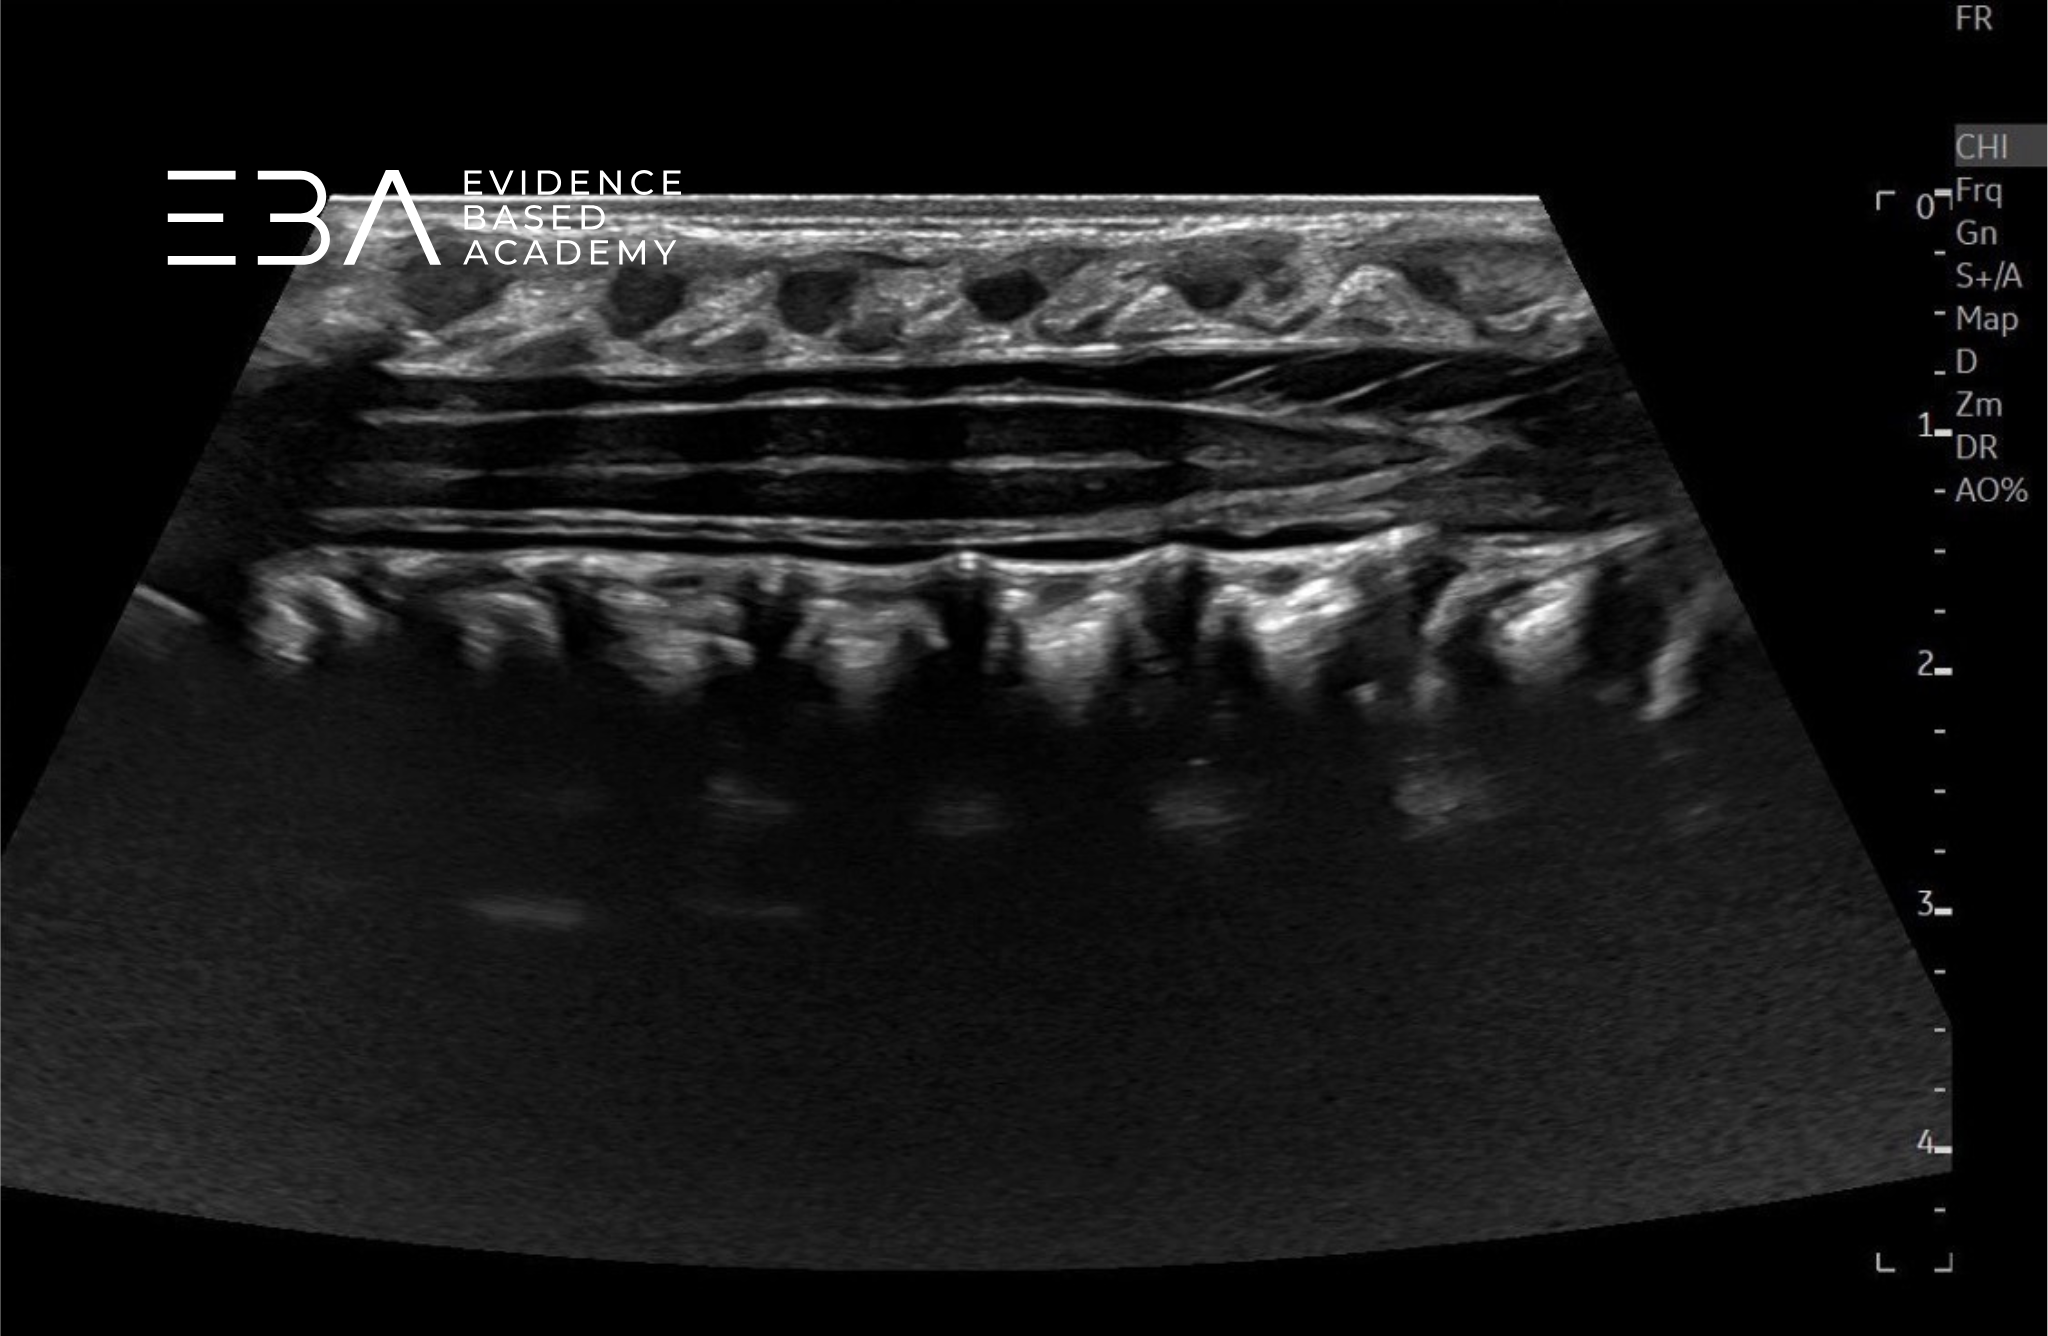

Obrazowanie dynamiczne

W trakcie USG kanału kręgowego należy przeprowadzić dynamiczną ocenę ruchomości rdzenia kręgowego i korzeni nerwowych. W niektórych przypadkach pomocne może być również USG w M-mode.

Należy pamiętać, że prawidłowy, nieuwięziony rdzeń również może nie wykazywać znaczącej pulsacji przez kilku pierwszych tygodni życia, co częściowo przypisuje się zmniejszonej objętości płynu mózgowo-rdzeniowego, wynikającej z fizjologicznego odwodnienia noworodków.

Przekrój podłużny przez kanału kręgowego – widoczna ruchomość ogona końskiego.